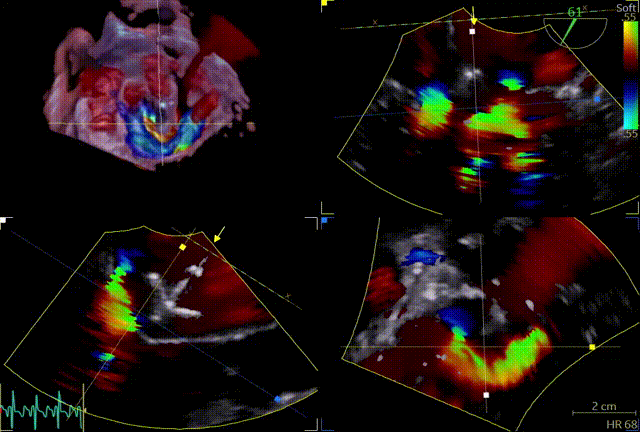

反流情况

术前TEE及左房压

1区

1区带彩